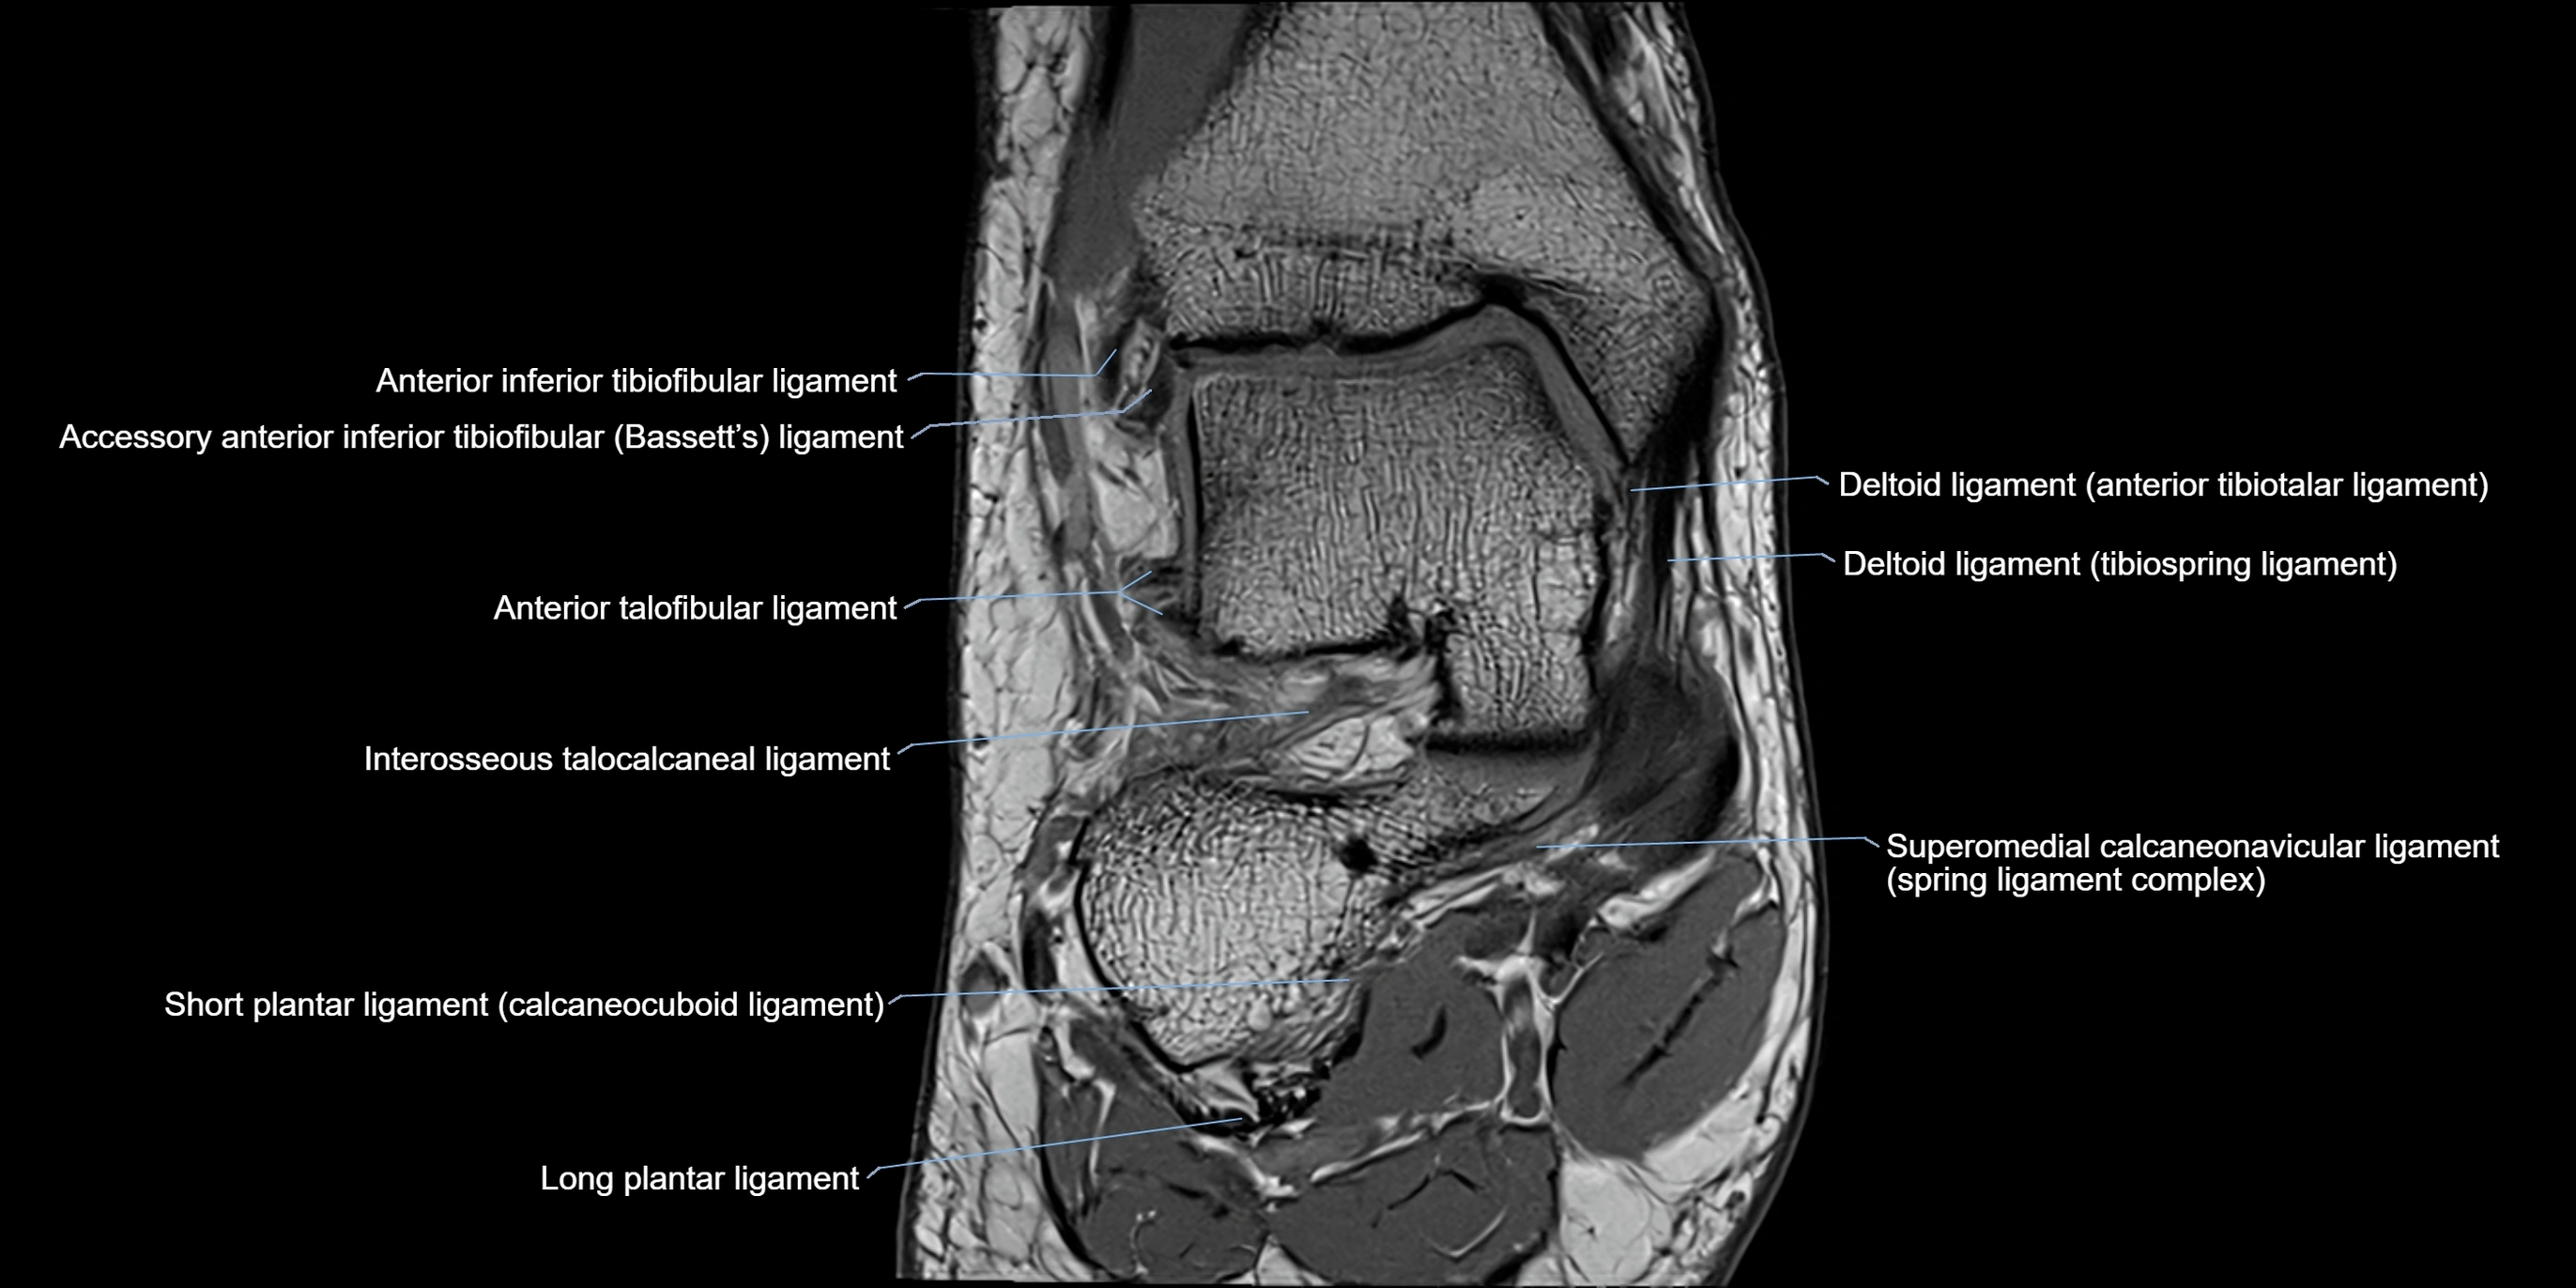

MRI image

image